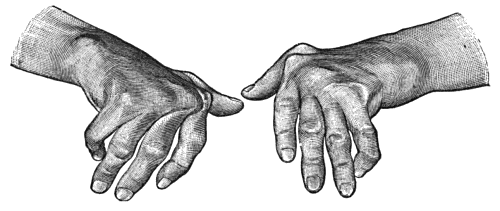

| 91. | To illustrate the Loss of Sensation produced by Division of the Median Nerve | 367 |

| 92. | To illustrate Loss of Sensation produced by Complete Division of Ulnar Nerve | 368 |